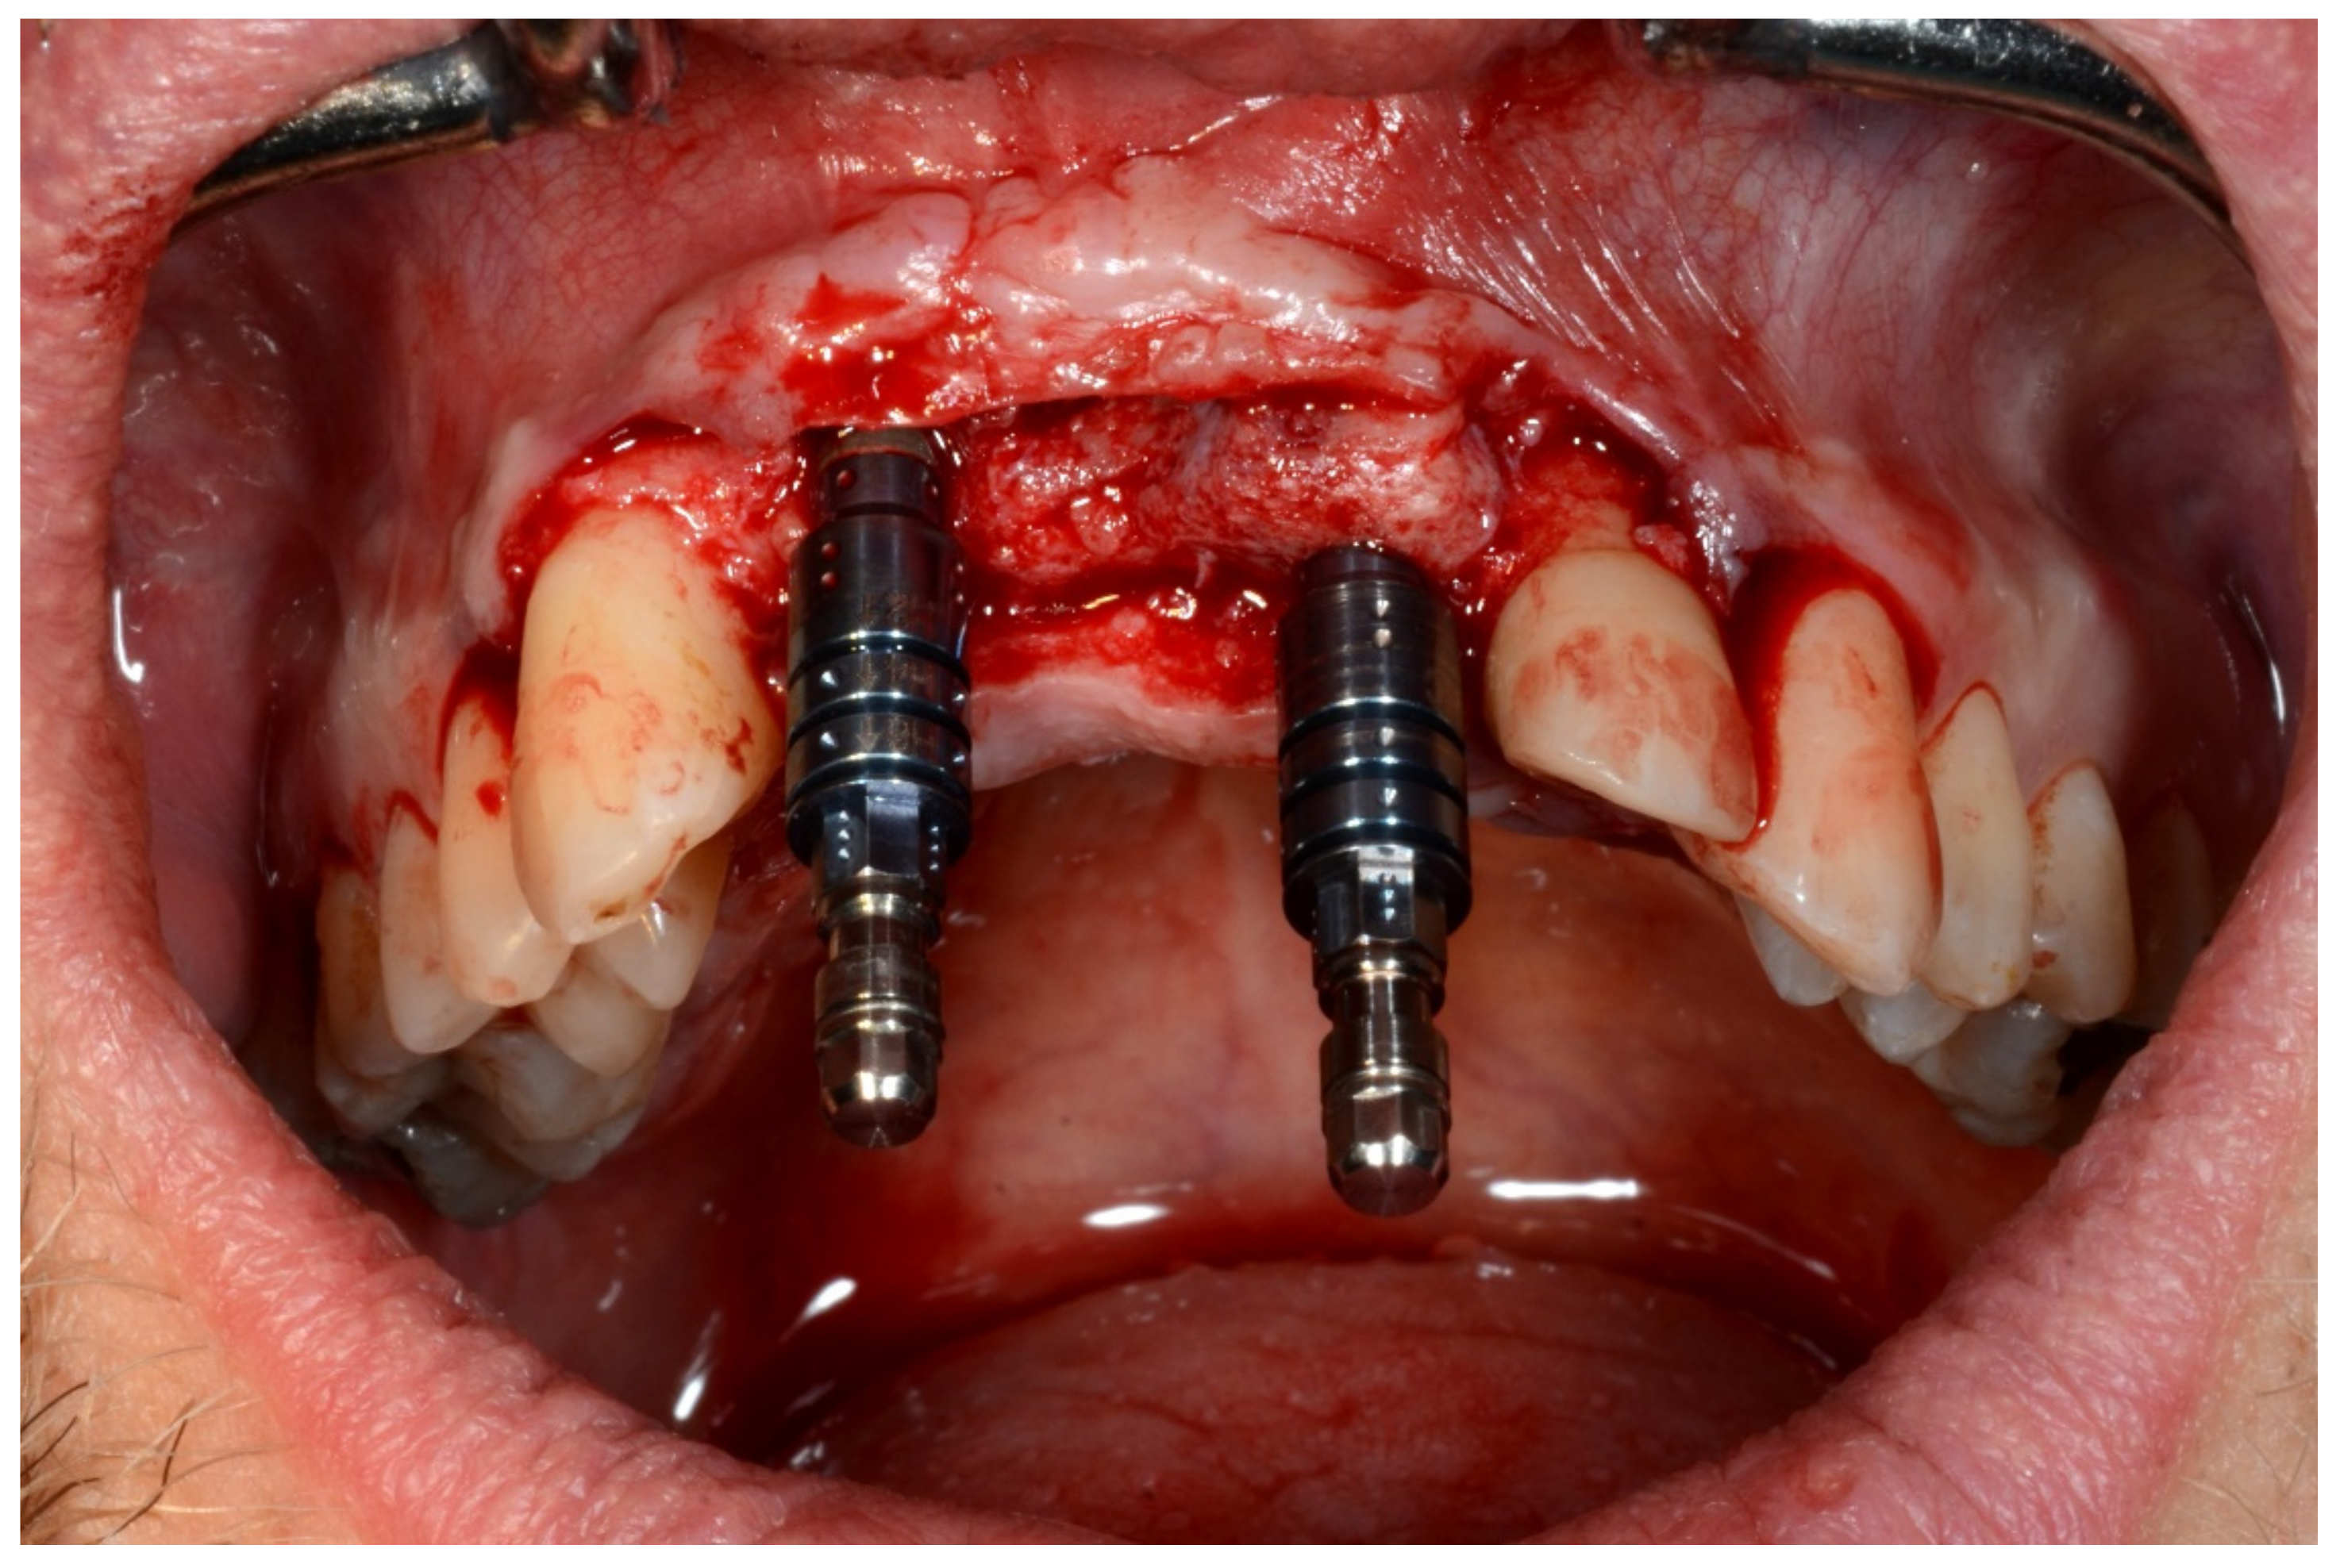

6.1.4. Intra-Operative Documentation: